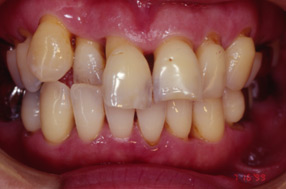

■歯周病治療例

歯周病の進行に伴う歯肉の

炎症と歯の移動が見られます。

歯周外科手術と同時に矯正で

歯周組織の再生と審美回復と

なりました。